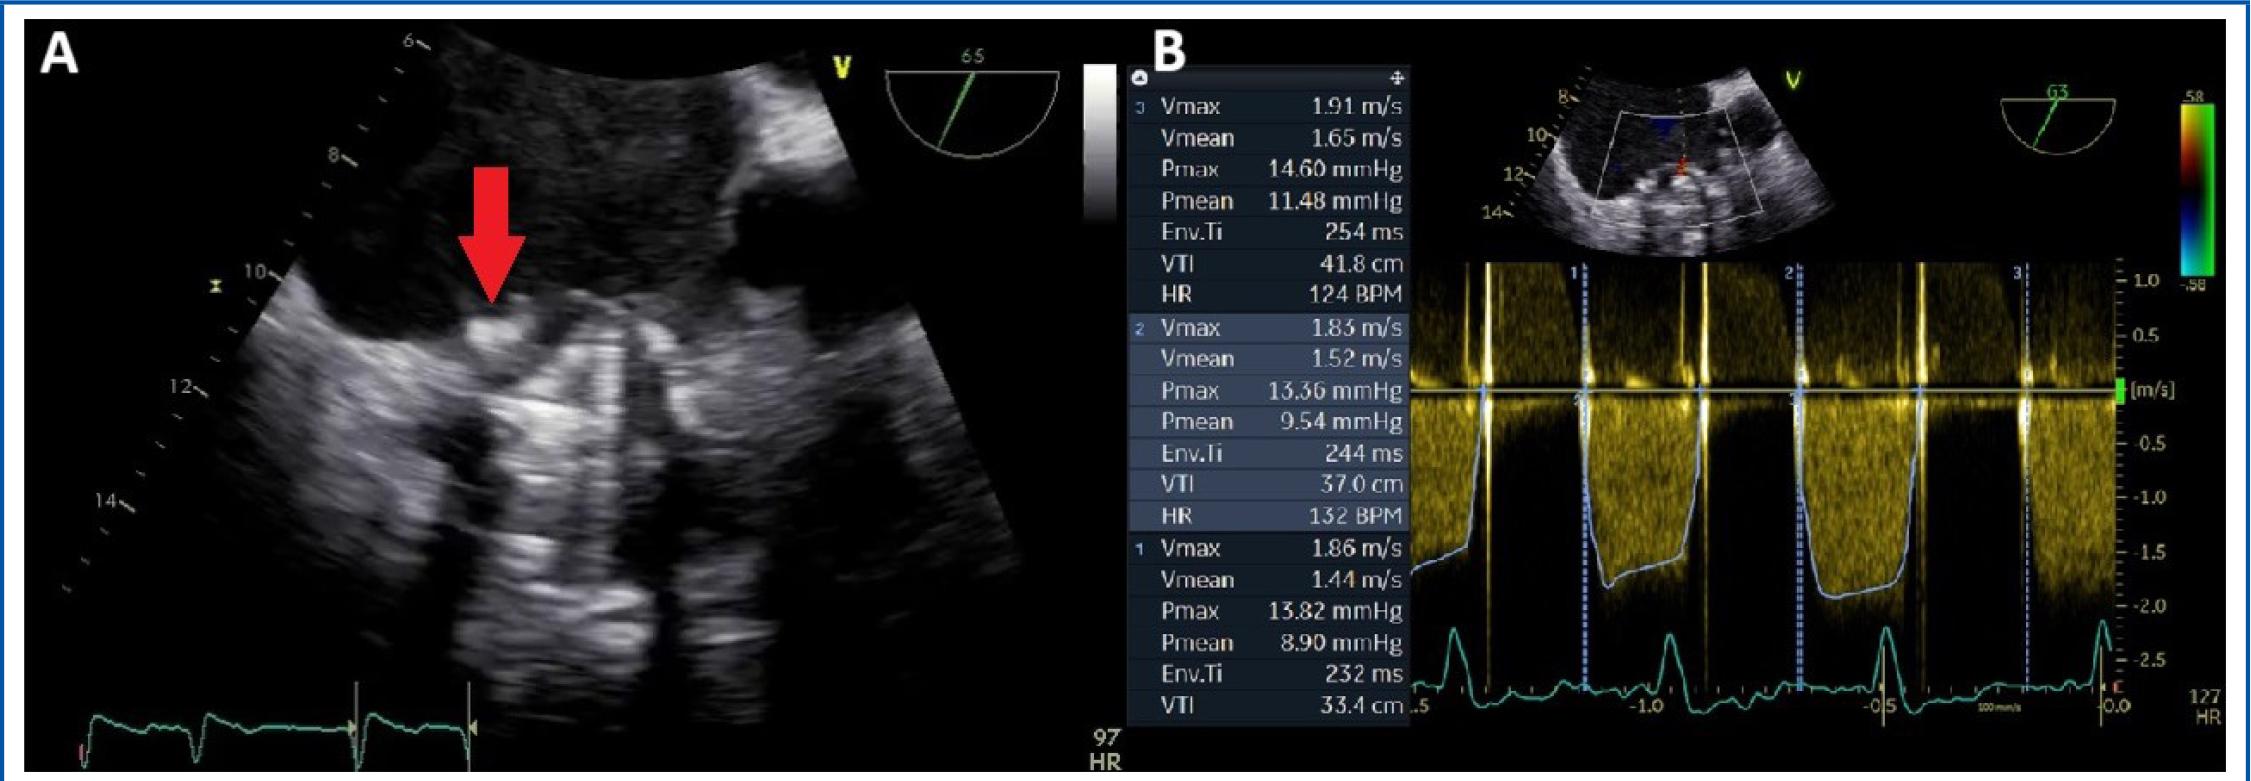

In 2014, the patient’s condition worsened due to an episode of aggravated heart failure. A TTE performed at that time revealed an immobile leaflet and severe obstruction of the tricuspid prosthesis. A comprehensive evaluation was conducted using multiple imaging modalities including transoesophageal echocardiography (TOE) and cinefluoroscopy in addition to TTE, which identified the underlying cause of the obstruction: both pannus and a small thrombus causing blockage of the lateral leaflet in a partially open position, in a patient already known with significant PPM (Figure 1). TOE images also revealed thrombosis of the pacing lead and in the left atrial appendage (LAA) (Figure 2).

Transoesophageal echocardiography. A) 2D-image showing a stuck leaflet of the tricuspid prosthesis due to both pannus and thrombus (red arrow). B) CW Doppler flow interrogation of the tricuspid prosthesis revealing high mean transvalvular pressure gradient (examination in atrial fibrillation).